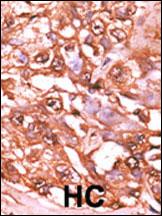

Formalin-fixed and paraffin-embedded human cancer tissue reacted with the primary antibody, which was peroxidase-conjugated to the secondary antibody, followed by AEC staining. This data demonstrates the use of this antibody for immunohistochemistry; clinical relevance has not been evaluated. BC = breast carcinoma; HC = hepatocarcinoma. |